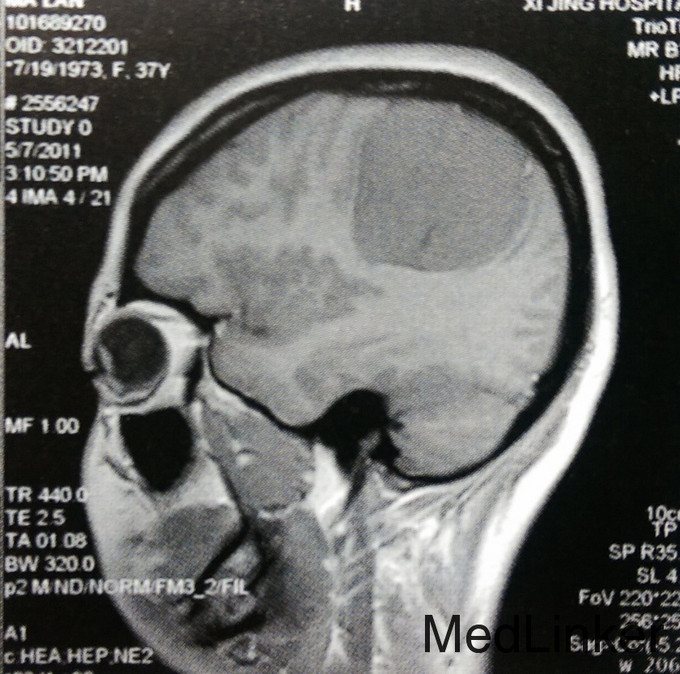

患者,女,37岁。主因左上肢麻木2年入院。 患者2年前无诱因出现左侧肢体麻木,无乏力、活动受限,未就诊。此后上述症状进行性加重,遂在当地医院以颈椎病对症治疗,未好转。行头颅MRI检查:右侧颞顶枕部见类圆形占位,大小约5.8cmх5.2cmх5.4cm,T1WI呈稍低信号,T2WI呈稍高信号,边缘尚清楚,压迫右侧脑室后角。Gd-DTPA增强后,明显强化,合并宽基底与脑膜相接,可见鼠尾征。门诊以“右顶叶巨大肿瘤”收入我科。无相关既往史、个人史及家族史。